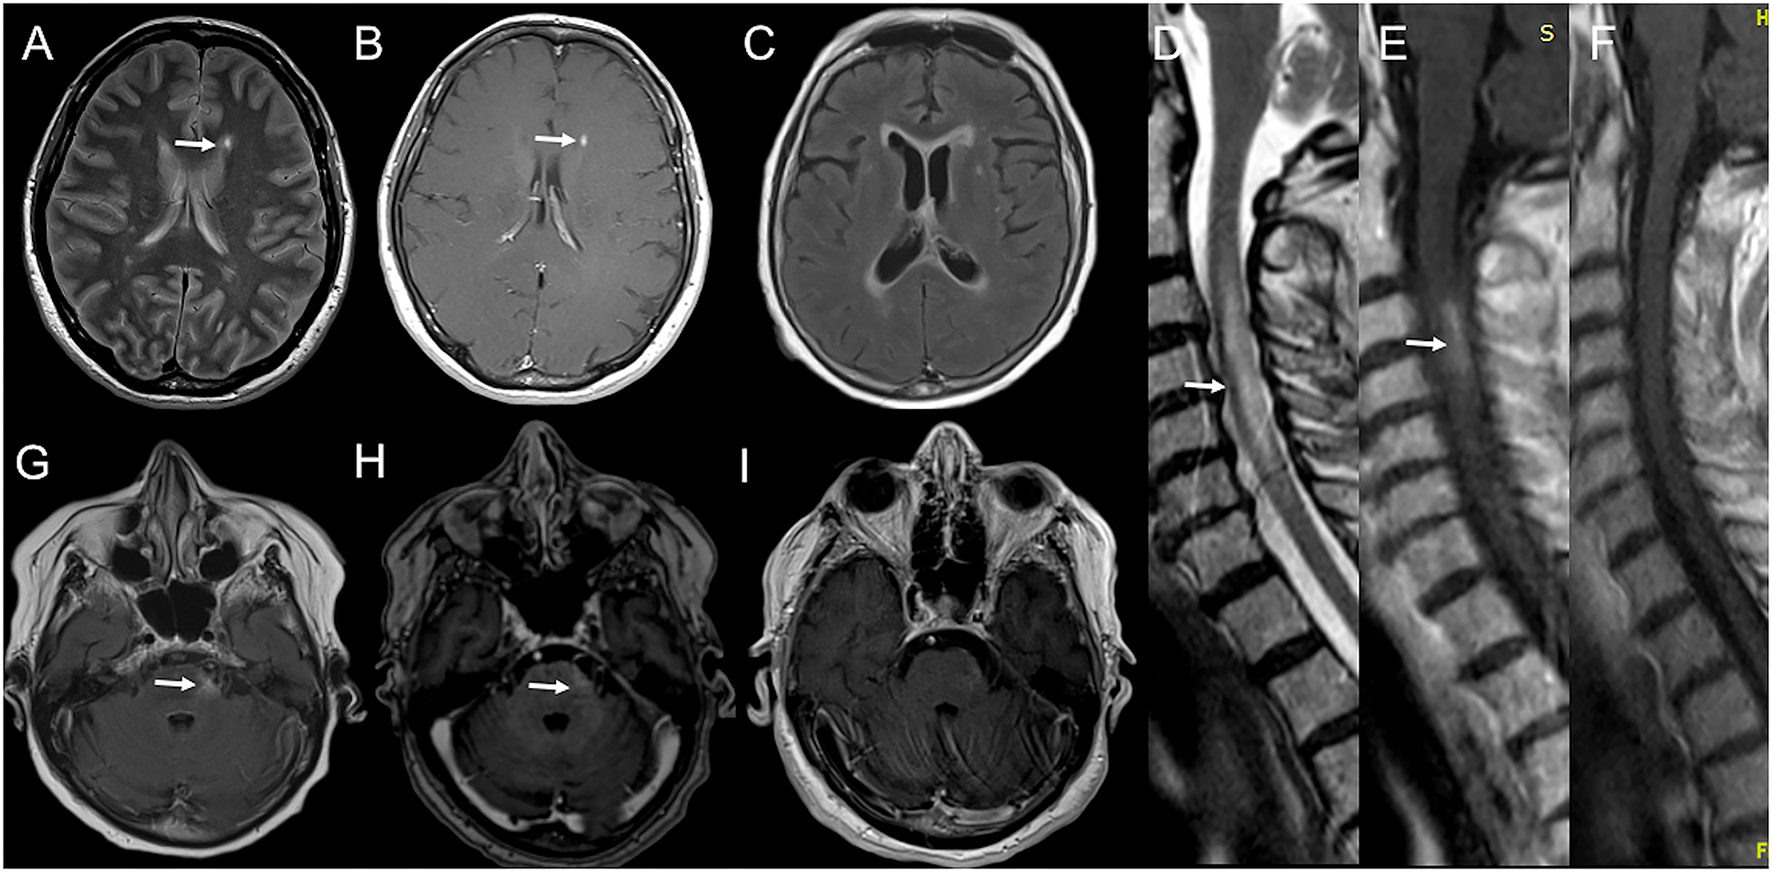

Figure 3

Serial brain and spinal cord MRI scans in Case 5 (A,B) and Case 6 (C–I). Case 5: (A) Brain MRI performed 28 days after BNT162b2 first dose, showing a new left lateral periventricular T2-weighted hyperintensity (arrow) with contrast enhancement [(B); arrow]. Case 6: (D) Spinal cord MRI obtained 12 days after BNT162b2 second dose, showing a T2-weighted hyperintensity from C2 to C7 with swelling (arrow) and gadolinium enhancement [(E); arrow]. (G) Brain MRI performed few days later showed a T2-weighted hyperintensity in left lateral pons (arrow) with blurred contrast enhancement [(H); arrow] and confluent supratentorial bilateral periventricular hyperintensities on FLAIR images (C). (I) 7-days MRI controls revealed the complete resolution of gadolinium enhancement of the left pontine lesion and the volume shrinkage of the cervical lesion with no more contrast enhancement on T1-weighted images (F).

A 53-year-old woman was diagnosed with MS at age 32 when she presented with paresthesia to her left limbs and a brain/spinal cord MRI showed dissemination in space and time. She was placed on interferon beta-1a with clinical and radiological stability over the next 10 years. In 2010, she developed numbness in her right arm and a new enhancing cervical lesion was detected in a spinal cord MRI. She was switched to Fingolimod with no evidence of disease activity until 2014 when she reported dysesthesia in her left face and a brain MRI revealed a new active lesion in the left frontal lobe. She was administrated a 5-day course of high-dose IVMP with full recovery. Since then, she remained stable at an EDSS of 2.5 at 6-month clinical controls and annual MRI follow-up. On 31st May 2021, she received the first dose of BNT162b2 vaccine and the second dose 35 days later. Two weeks after the first dose administration, she complained of gait imbalance and marked fatigue. A brain/spinal cord MRI—performed 14 days after symptoms onset—revealed a new left lateral periventricular T2-weighted hyperintensity with contrast enhancement (Figures 3A,B). Compared to the previous neurological exam, she showed moderate gait ataxia leading to an EDSS increase by 1 point. She was administrated a 5-day course of IVMP and clinically improved in a few weeks. At 6-months of control, she reported complete recovery (with EDSS returned to baseline) and the resolution of the new lesion enhancement at MRI. She continued with her current disease-modifying therapy (DMT).

A 75-year-old woman presented with right optic neuritis at age 60, partially resolved after OCS administration. Five years later she developed bilateral optic neuritis, treated with OCS with almost complete recovery. No brain/spinal cord MRI was performed at that time, and she started assuming chronic OCS with clinical stability over the following years. She developed Diabetes Mellitus and osteoporosis, complicated by a lumbar vertebral fracture for which she underwent surgical fixation in May 2021. Since then, she started using the right unilateral assistance in walking. On 3rd June 2021, she received the first dose of BNT162b2 vaccine and the second dose on 1st July. After 10 days, she developed dysesthesia and weakness in her right upper limb, followed by weakness in her legs. She was admitted to our emergency unit. On exam, she had four limbs weakness (with motor strength at MRC scale of grade 2/5 and 3/5 in her upper, and lower limbs, respectively), brisk osteotendinous reflexes, bilateral Babinski sign, and light touch hypoesthesia below D4 level. A spinal cord MRI showed a T2-weighted hyperintensity from C2 to C7 with swelling and gadolinium enhancement on T1-weighted images (Figures 3D,E). A brain MRI performed a few days later showed a T2-weighted hyperintensity in left lateral pons with blurred contrast enhancement and confluent supratentorial bilateral periventricular areas on FLAIR images (Figures 3C,G,H). Blood count, erythrocyte sedimentation rate, and C-reactive protein were normal. CSF analysis revealed normal cell count and protein level. No infectious agent was detected at CSF PCR, while IEP showed the presence of three OCBs (pattern II). Anti-AQP-4 antibodies were positive. Extensive serum panel for infectious diseases was unremarkable, as well as anti-connective tissue and anti-neural surface/onconeural antigens antibodies. Patient was administrated a 5-day course of high-dose IVMP. After 10 days, she showed improvement in limb motor performance, with strength at the MRC scale of grade 4/5 in all limbs. A new MRI revealed the complete resolution of enhancement in the left pontine lesion (Figure 3I) and the cervical area—also appeared significantly shrunk in volume (Figure 3F). The patient was planned to start physical therapy and a DMT (Rituximab/Eculizumab).